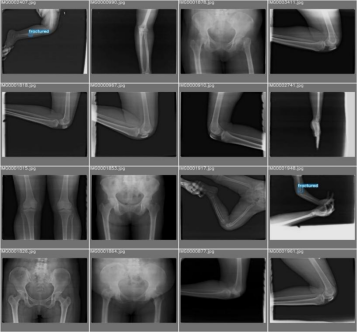

3.1 数据集构建和数据增强

骨折等骨损伤的X光片数据集从互联网中收集X光图像,对收集到的图像进行筛选,去除质量低下、不清晰或者与目标类别无关的图像。收集到的原始图像数据需要经过标注才能用于训练,数据标注是将图像中的每个目标用边界框标出,并为其分配相应的类别标签,这一步骤对于模型学习识别和定位目标至关重要,本设计选择LabelImg工具进行标注,如图3.1所示。

处理完成的数据集一共有3238张图片用于训练,449张图片用于验证。其中检测的类别为fractured(骨损伤),但在数据集中只有723个fractured目标。将处理过的数据集输入YOLO算法进行模型训练,数据集中的目标数量如图3.2左上角所示,其显示了fractured类别包含的样本数量;目标框的尺寸和数量如图3.2右上角所示,其展示了训练集中边界框的大小分布以及相应数量;目标框中心点相对于整幅图的位置坐标如图3.2左下角所示,其描述了边界框中心点在图像中的位置分布情况;数据集中目标相对于整幅图的高宽比例如图3.2右下角所示,其反映了训练集中目标高宽比例的分布状况。